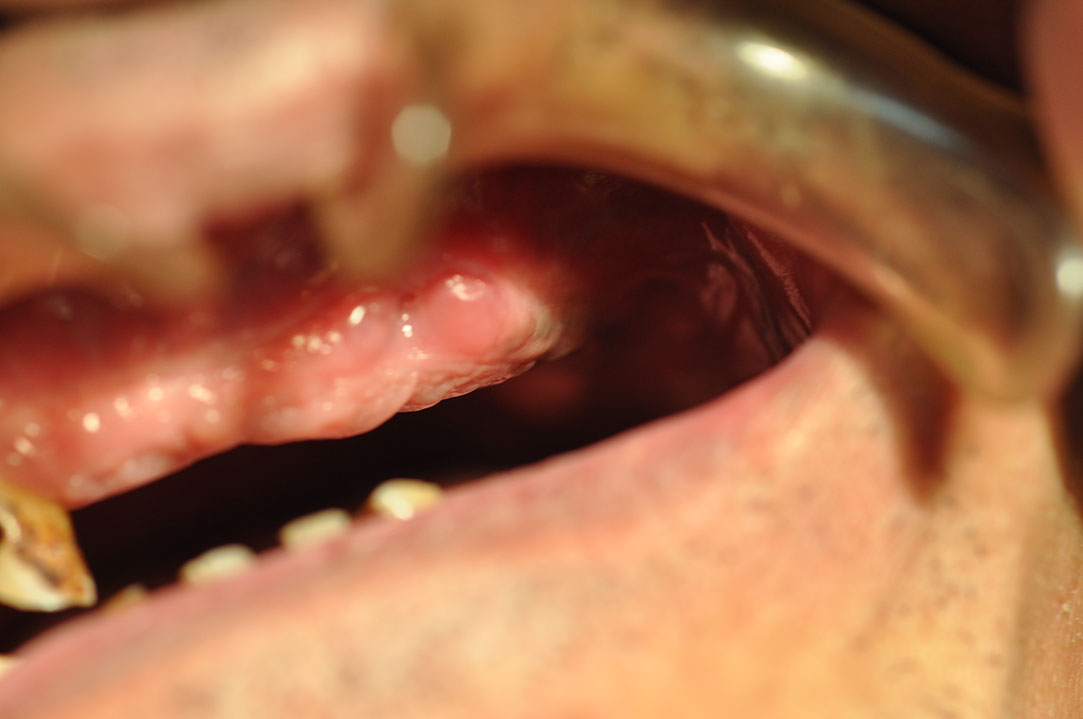

Implant 118a2.JPG